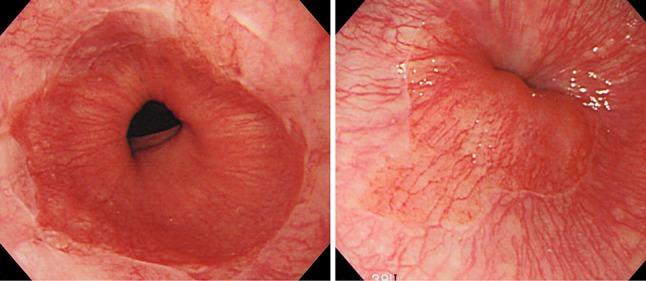

Japanese Classification of Esophageal Cancer, 11th Edition: part I.

Esophagus. 2017;14(1):1-36. doi: 10.1007/s10388-016-0551-7. Epub 2016 Nov 10.